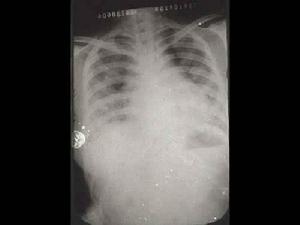

肺念珠菌病2、影像學檢查:兩肺紋理增深或呈瀰漫性小片狀或斑點狀陰影部分可融合成大片緻密影邊緣模糊形態,多變發展迅速病變大多位於中下肺野部分,病例伴胸膜改變慢性病變呈纖維條索狀陰影和代償性肺氣腫。

3、X線檢查:顯示兩肺紋理增多,或呈瀰漫性小片狀或斑點狀陰影,部分可融合成大片緻密影,邊緣模糊,形態多變,發展迅速。病變大多位於中下肺野,肺尖較少受累。

3.胸片可見小片狀或斑點狀陰影,部分可融合。